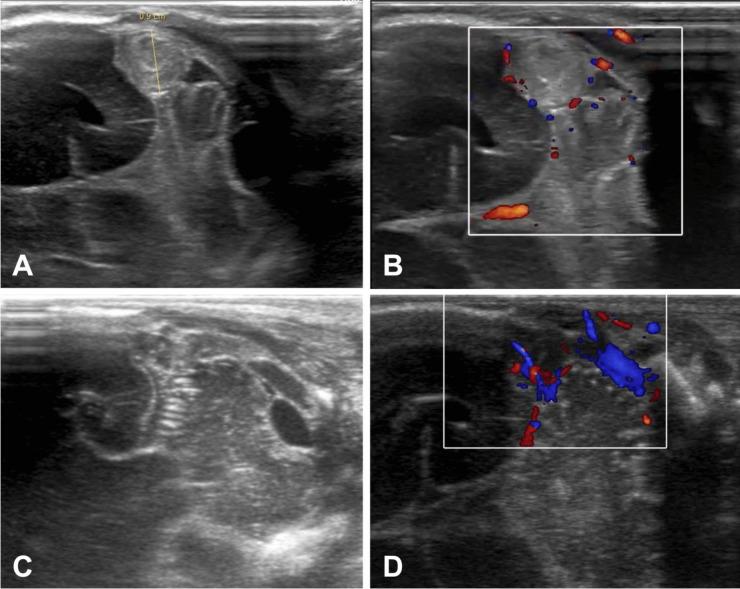

Cerebral sinus venous thrombosis (CSVT) is a serious condition in premature infants. Early diagnosis is crucial, as untreated CSVT can progress to severe complications such as delayed-onset intraventricular hemorrhage (IVH), which could lead to poor outcomes in this population.

This case highlights that serial cranial ultrasound can detect CSVT early, enabling prompt treatment and preventing subsequent complications.

We present the case of an extremely low birth weight infant diagnosed with CSVT based on cranial ultrasonography findings. The patient had no clinical symptoms or previously detected brain injury.

Anticoagulant therapy was initiated immediately after diagnosis. Clot resolution was observed on cranial ultrasound after 5 days and confirmed by magnetic resonance imaging (MRI) on the 82 day of life (36 + 4 weeks of gestational age).

This case shows the significant value of cranial ultrasound as a diagnostic tool in premature infants when MRI is not immediately available. Early detection and treatment using ultrasound may help prevent severe complications.